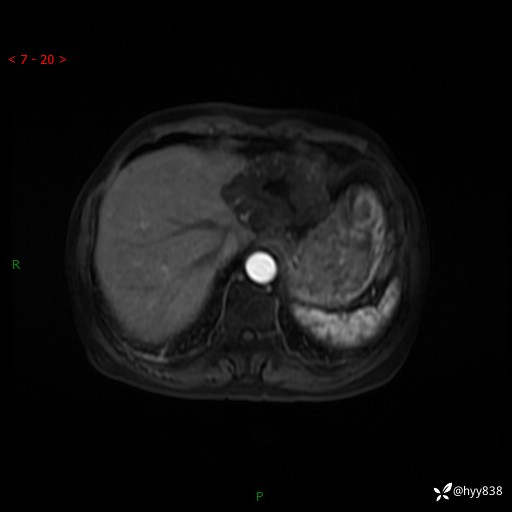

辅助检查:MRI

肝脏MRI平扫(同反相位)

T2WIfs+DWI

增强(动脉期+静脉期+延迟期)